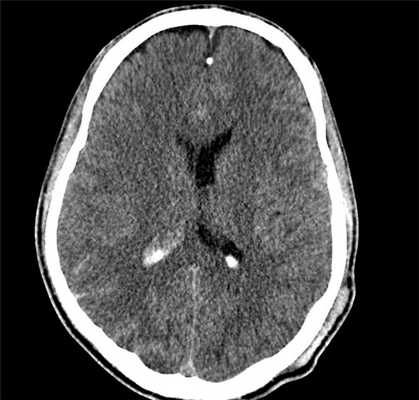

При определенном опыте клинический диагноз ДАП вполне возможен. Однако его всегда следует подкрепить КТ или МРТ. На КТ диффузное аксональное повреждение характеризуется увеличением объема мозга различной степени (вследствие его отека, набухания, гиперемии) со сдавлением боковых и III желудочка, субарахноидальных конвекситальных пространств, а также цистерн основания мозга. При этом часто выявляются мелкоочаговые геморрагии в белом веществе полушарий мозга, мозолистом теле, а также в подкорковых и стволовых структурах (рис. 1).

Вместе с тем еще в остром периоде обнаруживается довольно типичный для ДАП феномен скопления жидкости (с плотностными характеристиками ликвора) над лобными долями, преимущественно в передних отделах с одной или обеих сторон. При легких и среднетяжелых формах ДАП на КТ выявляются лишь признаки незначительного увеличения объема мозга либо компьютерная картина неотличима от нормальной. Повторные КТ-исследования, проведенные у больных с ДАП, обнаруживают довольно характерную динамику. Спустя 2-4 недели после травмы явления отека и набухания мозга регрессируют, мелкоочаговые геморрагии либо не визуализируются, либо становятся гиподенсивными. Вместе с тем начинают отчетливо вырисовываться базальные цистерны и конвекситальные субарахноидальные щели на фоне более или менее выраженной тенденции к расширению желудочковой системы. Вентрикуломегалия и другие признаки диффузного атрофического процесса часто в дальнейшем нарастают (см рис. 1).

КТ-картина диффузного аксонального поражения мозга характеризуется увеличением объема мозга, в результате которого под сдавлением находятся боковые и III желудочки, субарахноидальные конвекситальные пространства, а также цистерны основания мозга. Нередко выявляют наличие мелкоочаговых геморрагий в белом веществе полушарий мозга, мозолистом теле, подкорковых и стволовых структурах.